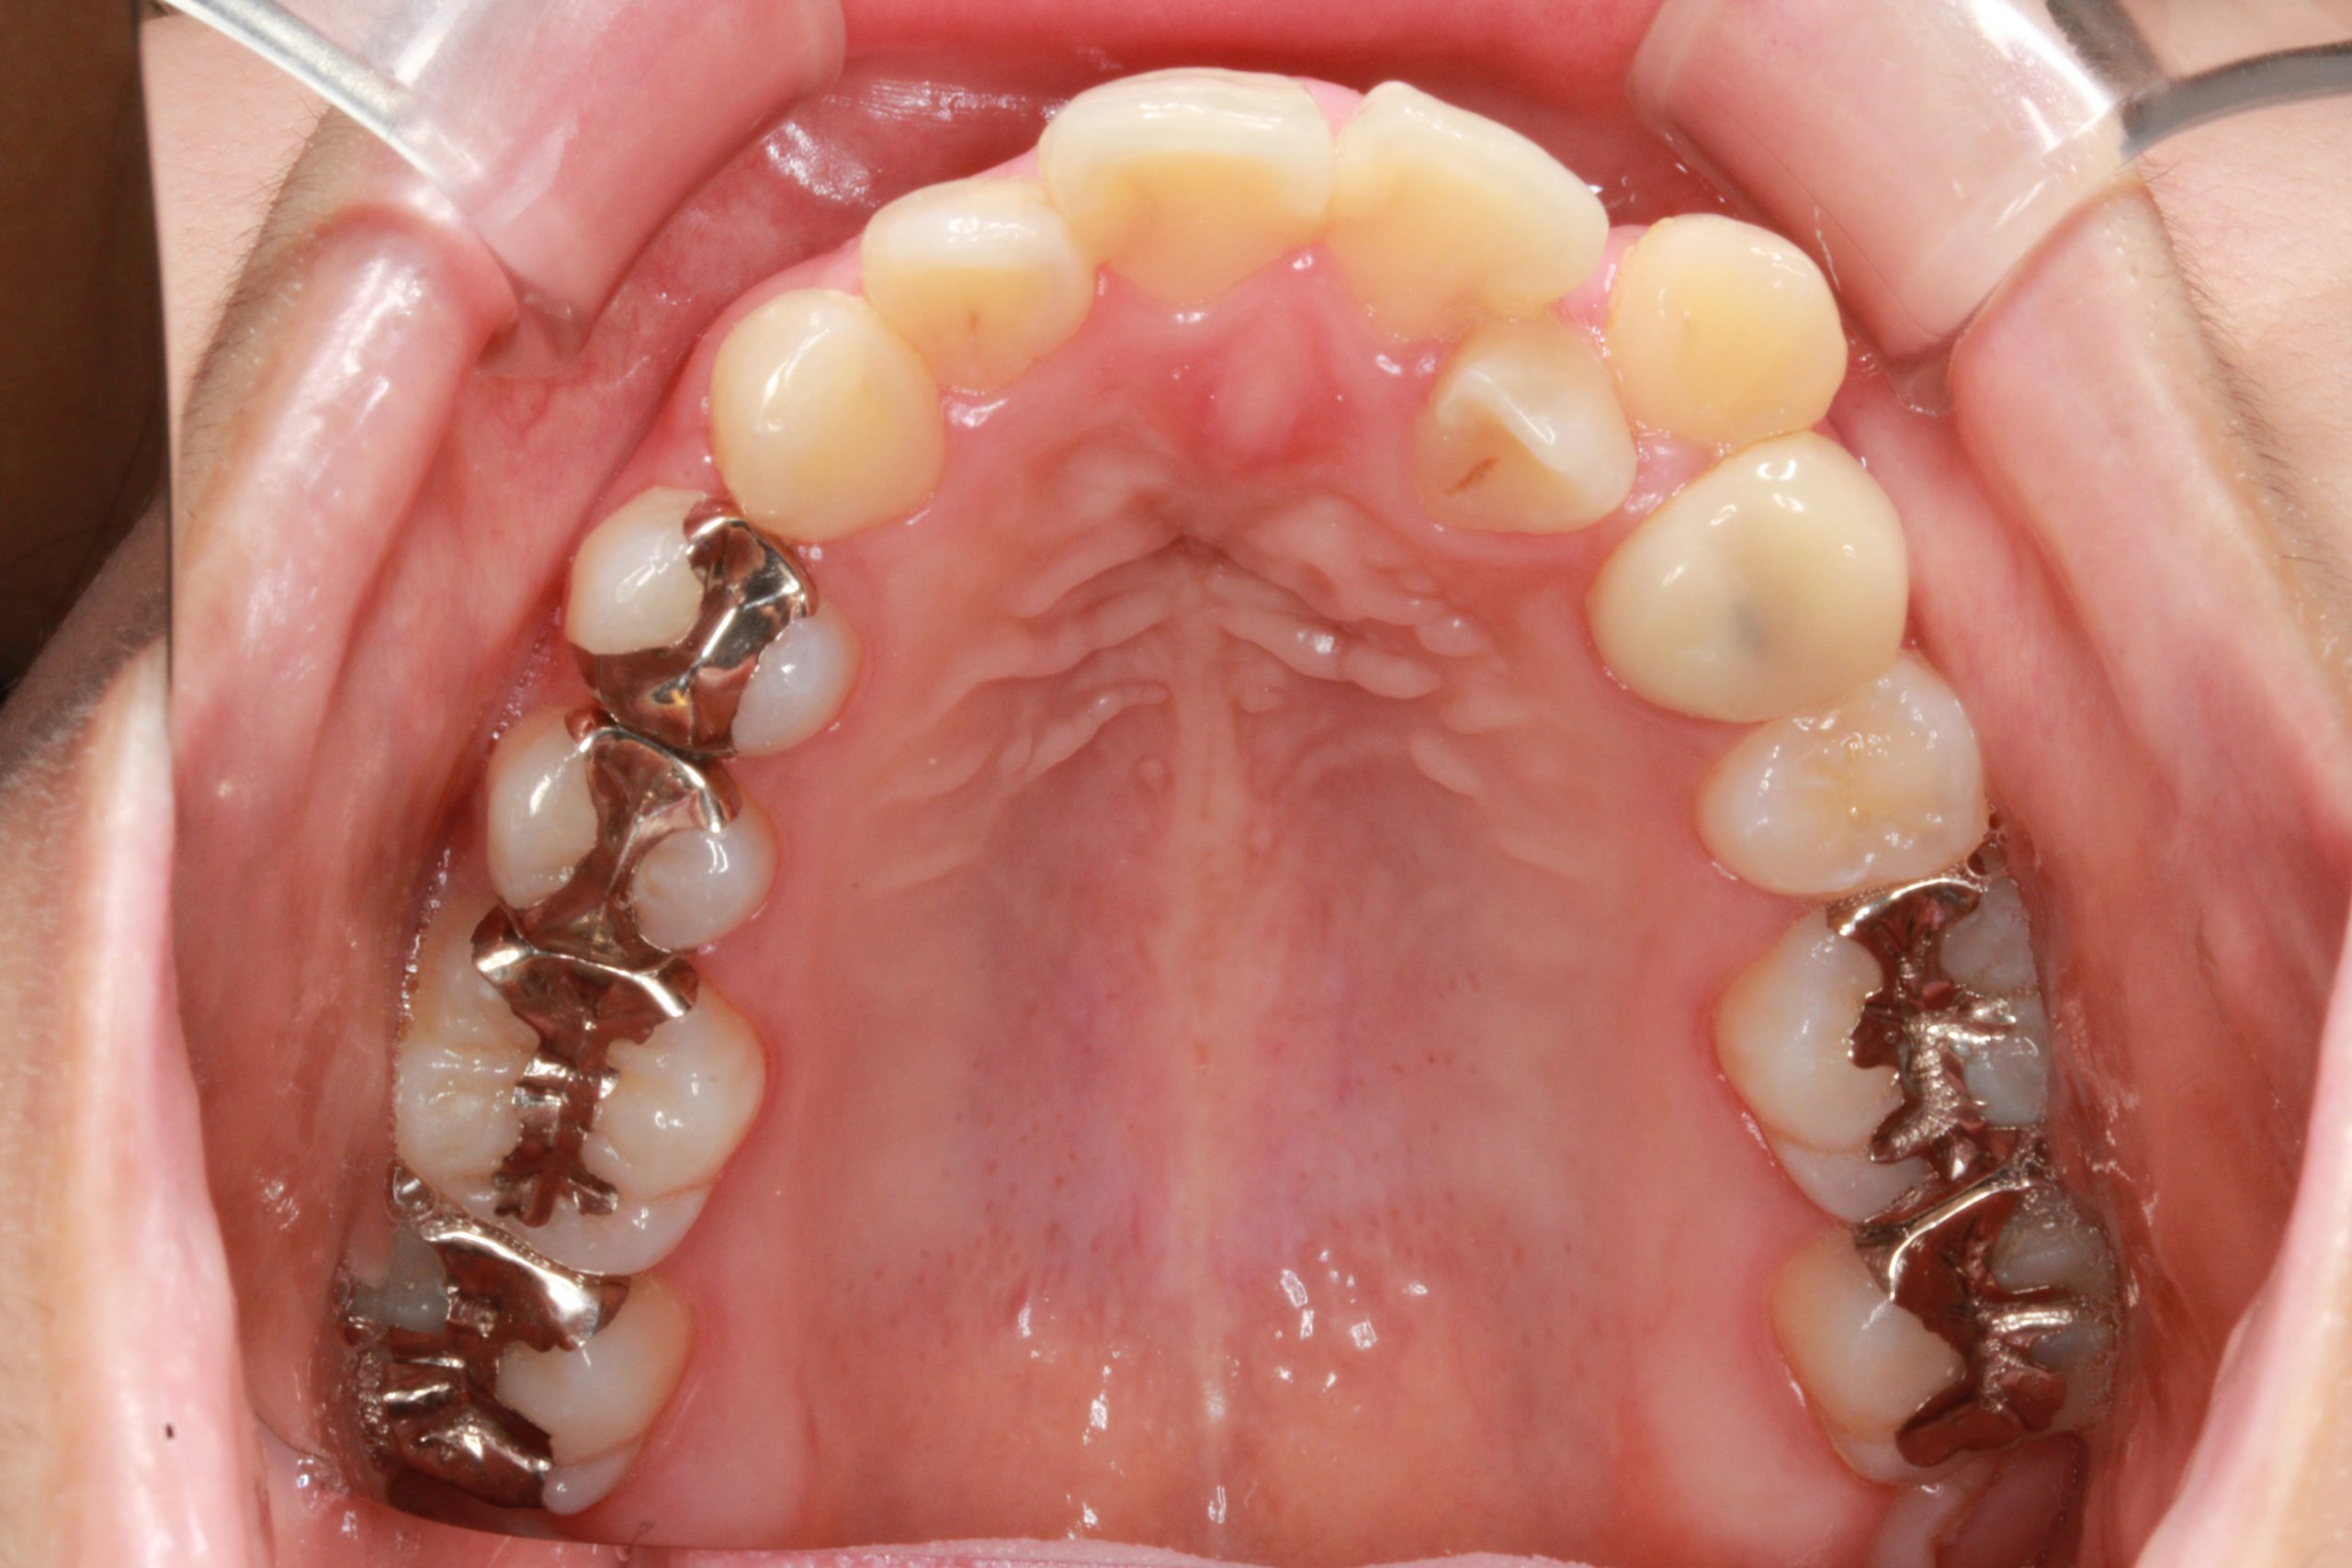

下の歯が出ている ・噛んだ時に、下の歯と上の歯がかみ合わない

| 主訴 | 下の歯が出ている ・かんだ時に、下の歯と上の歯がかみ合わない |

Before